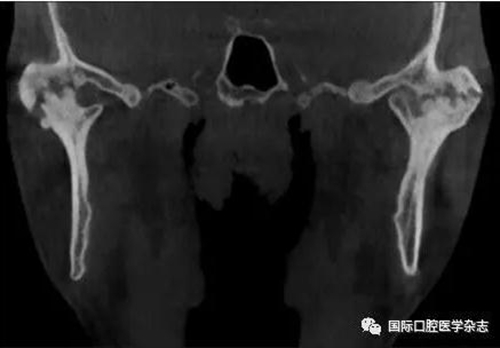

(4)關(guān)節(jié)強(qiáng)直(圖3):指因器質(zhì)性病變導(dǎo)致長期開口困難或完全不能開口??煞譃殛P(guān)節(jié)內(nèi)強(qiáng)直和關(guān)節(jié)外強(qiáng)直。關(guān)節(jié)內(nèi)強(qiáng)直是由于一側(cè)或兩側(cè)關(guān)節(jié)內(nèi)發(fā)生病變,造成關(guān)節(jié)內(nèi)的纖維性或骨性粘連,也有人稱為真性關(guān)節(jié)強(qiáng)直。關(guān)節(jié)外強(qiáng)直是病變位于關(guān)節(jié)外上下頜間皮膚、黏膜或深層肌肉組織,形成頜間瘢痕攣縮(圖4),也有人稱為假性關(guān)節(jié)強(qiáng)直[7]。5)顳下頜關(guān)節(jié)感染:常由下頜關(guān)節(jié)附近化膿性病灶所致。多見于兒童中耳炎、腮腺炎等。此外還可由全身性傳染性疾病如麻疹、猩紅熱等引起。6)顳下頜關(guān)節(jié)外傷(圖5):外傷是引起開口受限的常見因素之一,最常見于下頜骨髁突骨折引起下頜運(yùn)動(dòng)受限[8]。

圖 3 關(guān)節(jié)內(nèi)強(qiáng)直